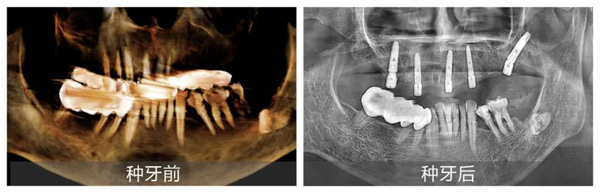

新橋口腔成都蜀漢院區(qū)種植專科主任姜辰醫(yī)生接診后,以專業(yè)嚴謹?shù)膽B(tài)度為張叔叔進行了全面細致的檢查。通過CBCT檢查、口內(nèi)檢查及問診,姜辰迅速判斷張叔叔的牙痛是由長期牙髓炎導致牙齒腐壞,牙齦萎縮所致,牙齒已無法保留。在獲取張叔叔詳細體檢報告并進行全面綜合評估后,姜辰主任醫(yī)療團隊確認其身體狀況能夠接受手術,果斷制定了上半口即刻種植修復方案。該方案既能滿足張叔叔盡快恢復咀嚼功能的需求,又最大程度地減輕了他的痛苦,縮短了治療周期。